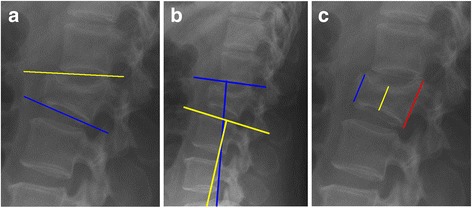

For study purposes standing anteroposterior and lateral roentgenograms pre- and approximately 9 months postoperatively and at latest follow-up after removal of the instrumentation were analysed (3 to 91 months after removal of the instrumentation). In eight out of the 12 patients with lumbar fractures, flexion-extension roentgenograms were available at latest follow-up. All roentgenograms were evaluated by two independent observers who were not involved in patient care (JK, FH). Mean values of their measurements were calculated. Interclass correlation coefficient was used to determine the conformity between the two observers. The wedge angle (WA, Fig. 1a), the segmental kyphosis angle (KA, Fig. 1b) and the ratios between both the anterior- and the posterior vertebral body height (APVBHr, Fig. 1c) and the central- and posterior vertebral body height (CPVBHr, Fig. 1c) were determined. Residual mobility was reported when both observers noted more than three degrees of range of motion between the flexion and extension roentgenograms in either the proximal or distal adjacent segment. Range of motion was defined as described by Tanz et al. [24] CT-scans were taken before and after the initial surgery to evaluate spinal canal encroachment, cement leakage and malposition of the instrumentation in all patients except for one.

Fig. 1.

a WA: Angle between the superior- and inferior endplate of the fractured vertebra. b SK: Angle between the adjacent vertebral endplates of the fractured vertebra. c APVBHr resp. CPVBHr: Ratios between the anterior- resp. central vertebral height in relation to the posterior vertebral height